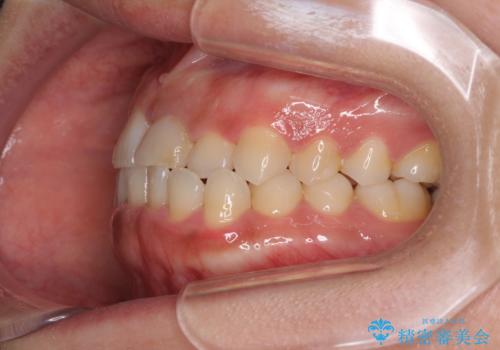

前歯のクロスバイトと変色した歯 ワイヤー矯正とセラミック治療

ワイヤー矯正により矯正治療を行った後に、前歯の補綴治療を行うこととしました。

変色してしまった前歯は、反対側の歯と比べて歯肉が覆い被さっていたため、骨整形を含めた歯周外科処置を行い、歯肉ラインを整えることとしました。

歯周外科処置を行うかどうかは非常に悩んでいらっしゃいましたが、範囲がそれほど広くないため術後の痛みも強くないだろうということで、処置を行うこととなりました。